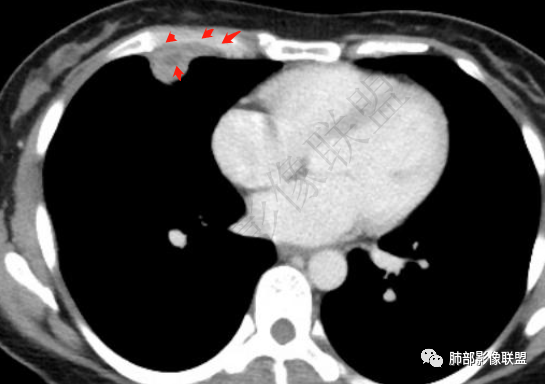

一月后复查,肺内病灶密度增高,边缘收缩,体积缩小,提示渗出朝增生转变;胸膜病灶缩小。

1.胸膜多发结节,边缘比较光滑,累及胸壁(胸痛也符合,一年),表现为脂肪间隙密度增高,最大的病灶累及肺内,附近有渗出,但是无放射状表现,增强中央有坏死灶,一月后似有缩小,肋骨完整未见破坏,支持炎性可能大!

2.肺内多发斑片影,边缘光滑,支持炎性特点,不符合恶性侵犯的特点,一般恶性肿瘤侵犯肺内往往边界不清,复查附近病灶有收缩,更加支持炎性病变;

胸膜区病灶及肺内病灶符合炎性改变,支持一元论炎性。